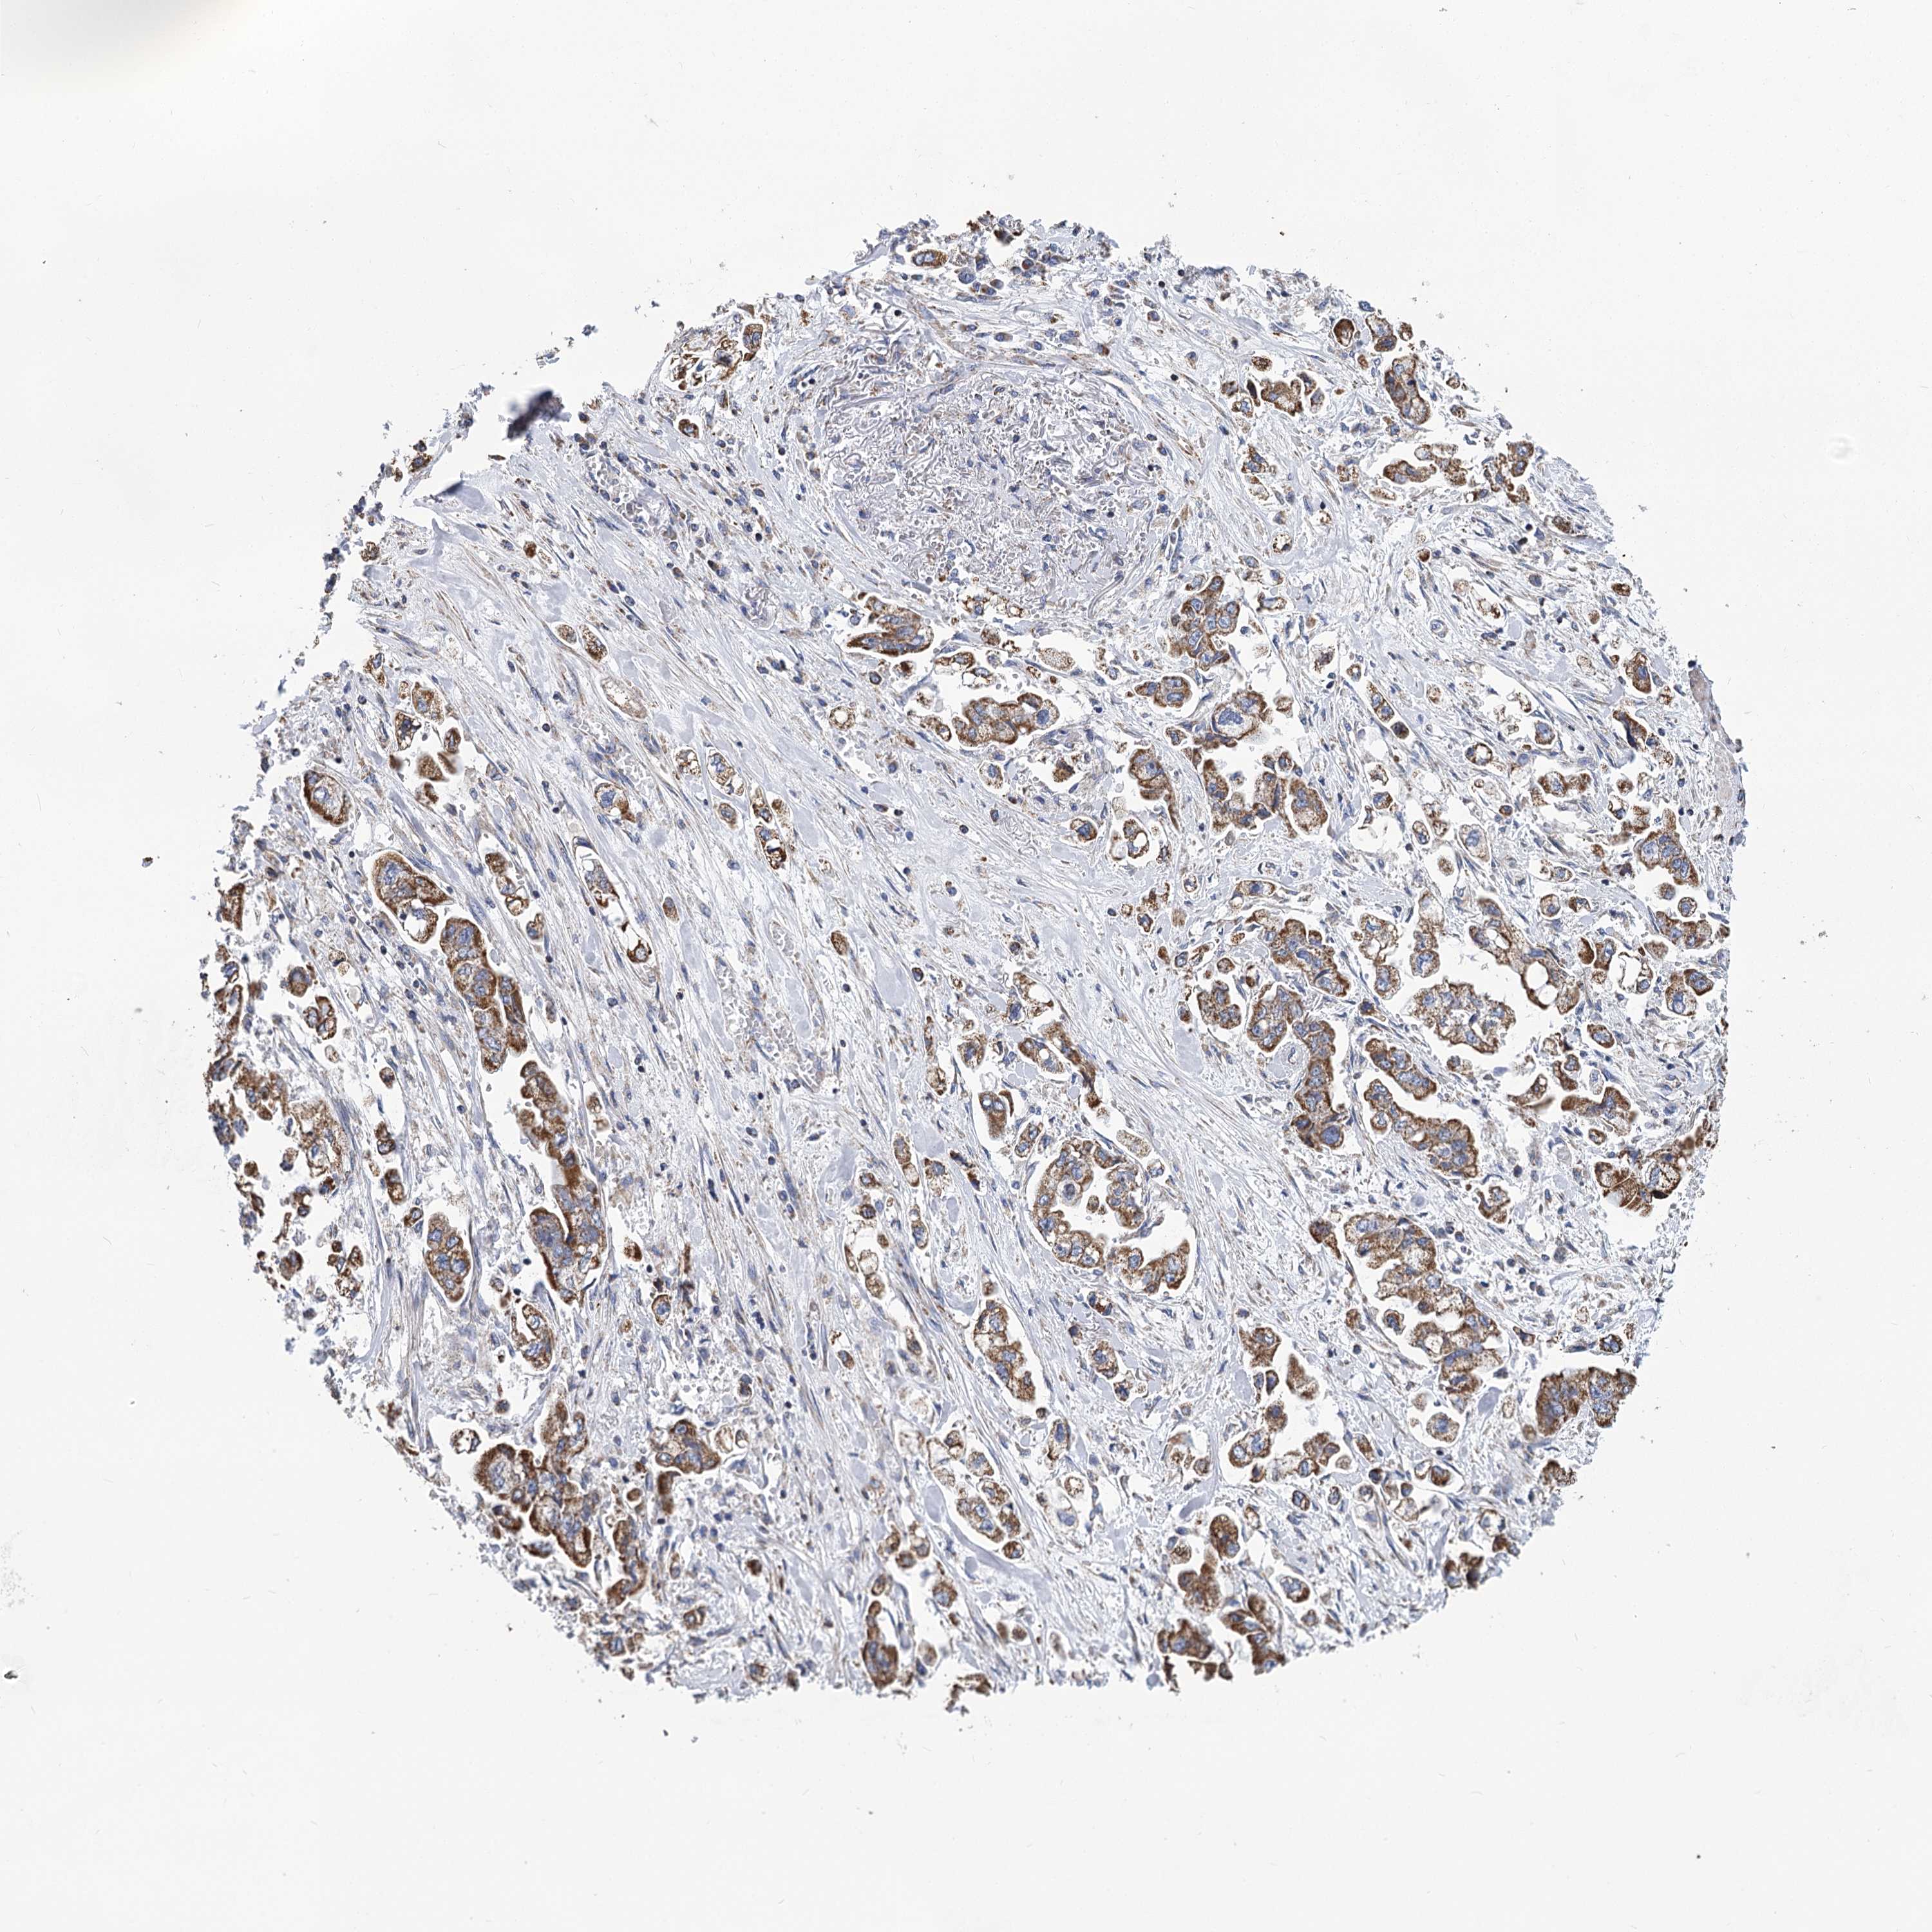

STOMACH CANCER - Protein expressioni

A mouse-over function shows sample information and annotation data. Click on an image to view it in a full screen mode. Samples can be filtered based on level of antibody staining by selecting one or several of the following categories: high, medium, low and not detected. The assay and annotation is described here.

Note that samples used for immunohistochemistry by the Human Protein Atlas do not correspond to samples in the TCGA dataset.

Antibody stainingi

Antibody staining in the annotated cell types in the current human tissue is reported as not detected, low, medium, or high, based on conventional immunohistochemistry profiling in selected tissues. This score is based on the combination of the staining intensity and fraction of stained cells.

Each image is clickable and will lead to virtual microscopy that enables deeper exploration of all samples and also displays staining intensity scores, fraction scores and subcellular localization as well as patient and tissue information for each sample.

Antibody HPA038668

Antibody HPA038669

Staining

High

Medium

Low

Not detected

Intensity

Strong

Moderate

Weak

Negative

Quantity

>75%

75%-25%

<25%

None

Location

Nuclear

Cytoplasmic/membranous

Cytoplasmic/membranous,nuclear

Adenocarcinoma, NOS

Adenocarcinoma, High grade